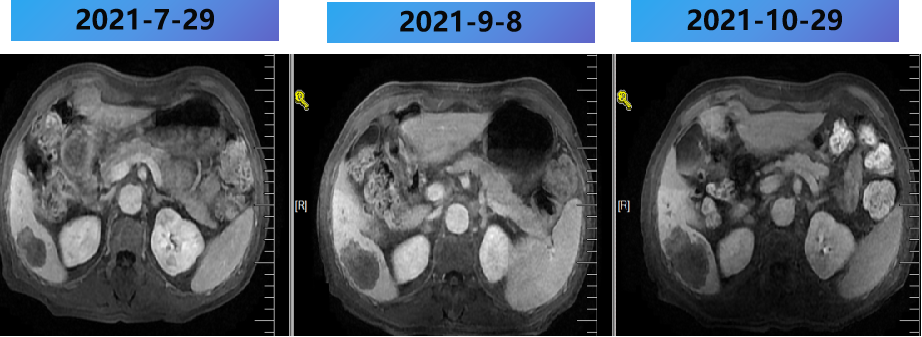

2021-2-20 (术后8m) 当地复查腹部MRI:肝脏多发转移瘤消融术后,较2021-1-5病变数目增多,体积增大。

2021-2-25至2021-7-15 更换方案为bev+伊立替康+雷替曲塞 9周期,部分病灶稳定(SD)。

2021-2-25至2021-7-25 更换方案为bev+伊立替康+雷替曲塞 9周期,部分病灶PD。

2021-2-25至2021-7-25 更换方案为bev+伊立替康+雷替曲塞 9周期,肺内病灶稳定(SD)。

西妥昔单抗联合阿帕替尼+PD-1抑制剂 2周期,出现蛋白尿,后调整为西妥昔单抗联合PD-1抑制剂,评价PD。